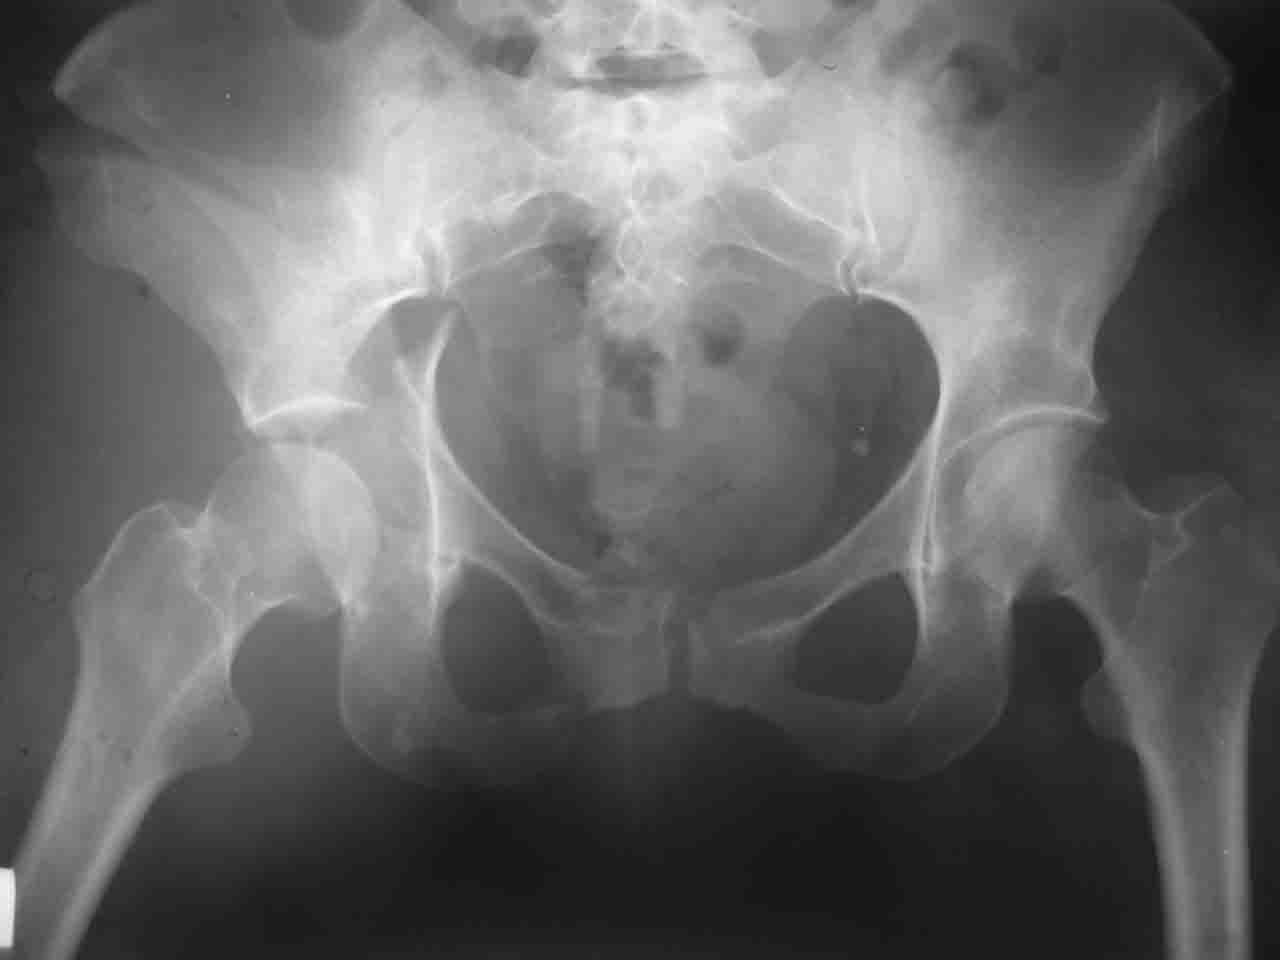

Снимки и схема